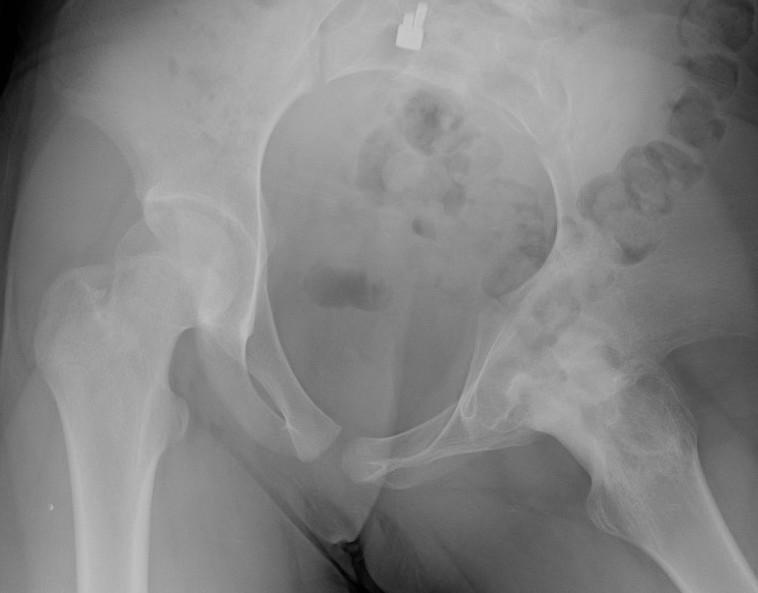

Xray

Normal with transient synovitis

Hip subluxation with septic arthritis

Septic arthritis

SCFE / Perthes